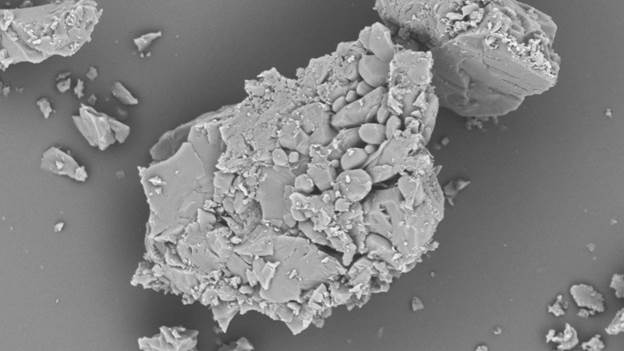

Для систем с модифицированным высвобождением СЭМ раскрывает взаимосвязь между внутренней архитектурой и кинетикой высвобождения. Например, хлорид калия в исходном состоянии характеризуется кубической кристаллической решеткой (рис. 2а).

Рис. 2а — Кубические кристаллы хлорида калия.